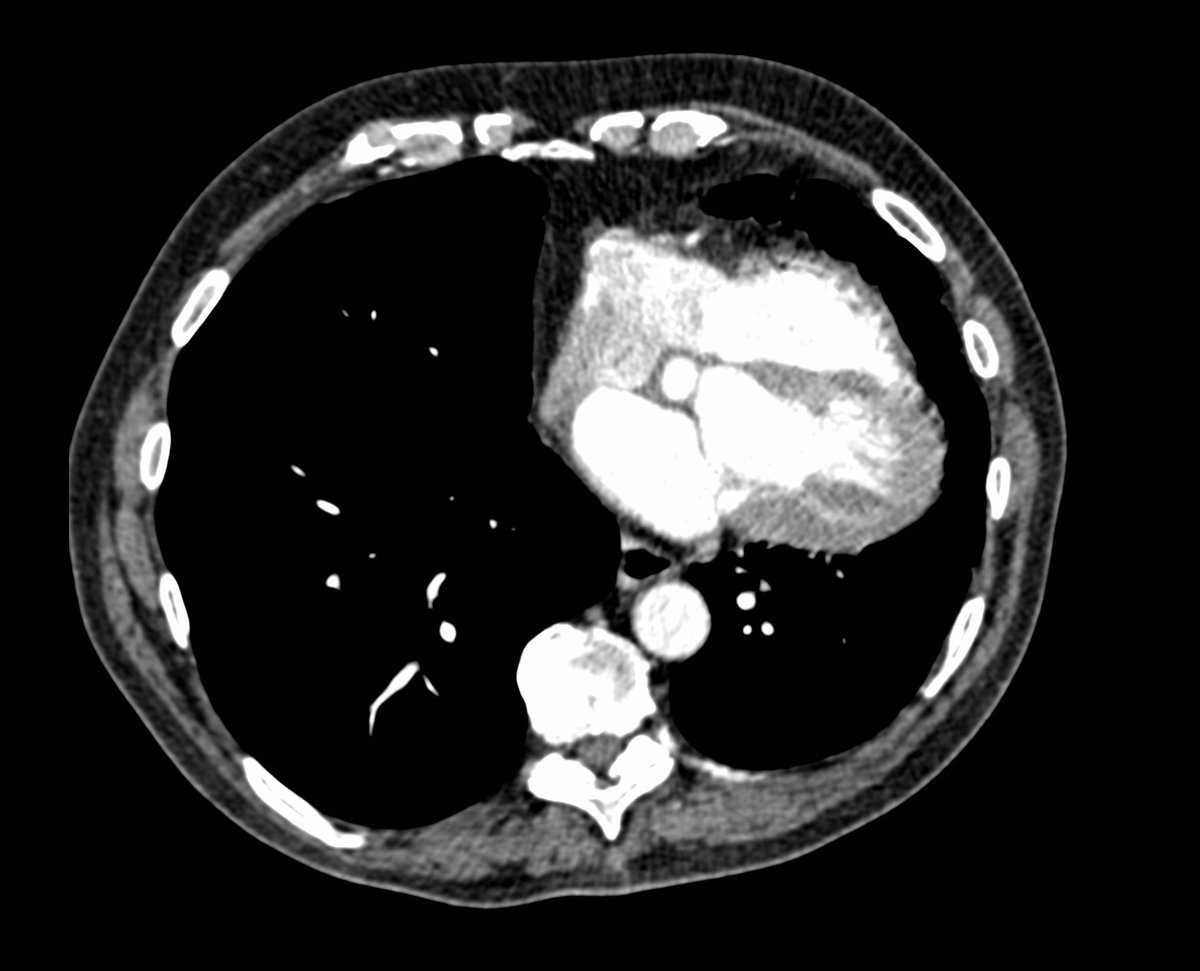

Friday conundrum. Routine chest radiograph and subsequent CT Thorax. Can you see anything abnormal on these images? Can you put it all together? Answers tomorrow.

#FOAMrad#FOAMed#FRCR#radiology#radiologists#CardioEd#cardiotwitter#RadRes#RadReg#meded Have a good weekend! pic.twitter.com/bkLPj1BPTa